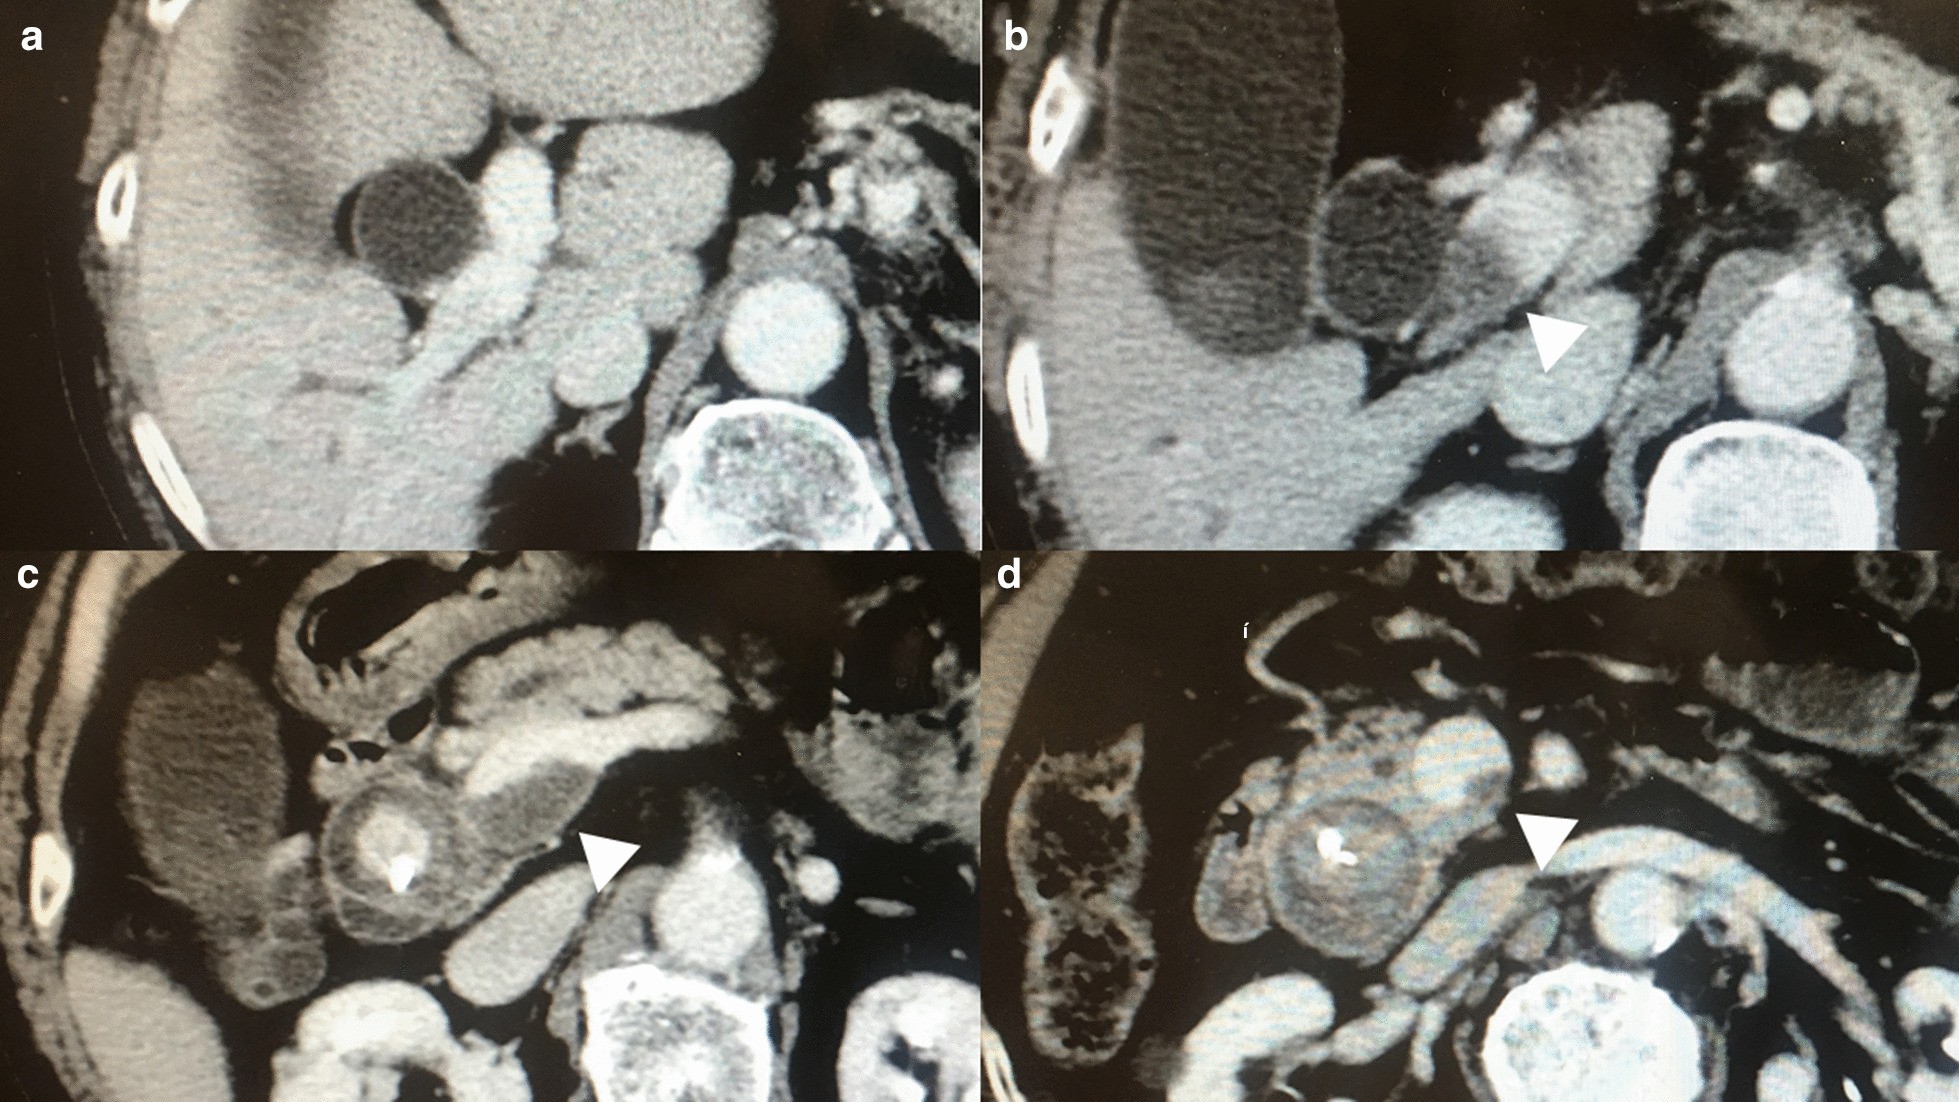

Fig. 2

Findings of the portal vein thrombosis in the preoperative period. The portal vein thrombosis (PVT) (White arrowheads) extended from the superior mesenteric vein (d) to the portal trunk (b). Although the PVT caused considerable stenosis at the level of the confluence of the superior mesenteric vein and the splenic vein (c), it did not reach the bifurcation of the right and left portal veins (a)